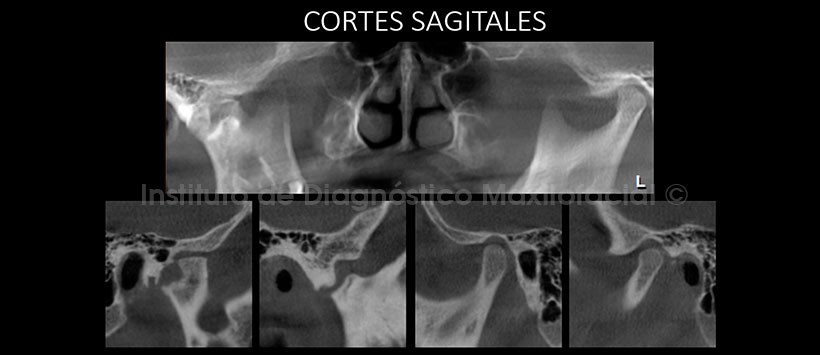

La tomografía computarizada de haz cónico, mediante los cortes sagitales, muestra de manera más clara la alteración de la morfología de la cavidad glenoidea, del cóndilo y del cuello del cóndilo. A nivel del cóndilo se observa que la mencionada alteración es dependiente de los contornos anterior, superior y posterior (Fig. 2). En la misma zona, mediante los cortes coronales, se aprecia la pérdida de la concavidad y el aumento del grosor de la cortical de la cavidad glenoidea; así como, el compromiso del contorno lateral del cóndilo (Fig. 3). Signos imagenológicos compatibles con una Anquílosis Fibrosa Unilateral.